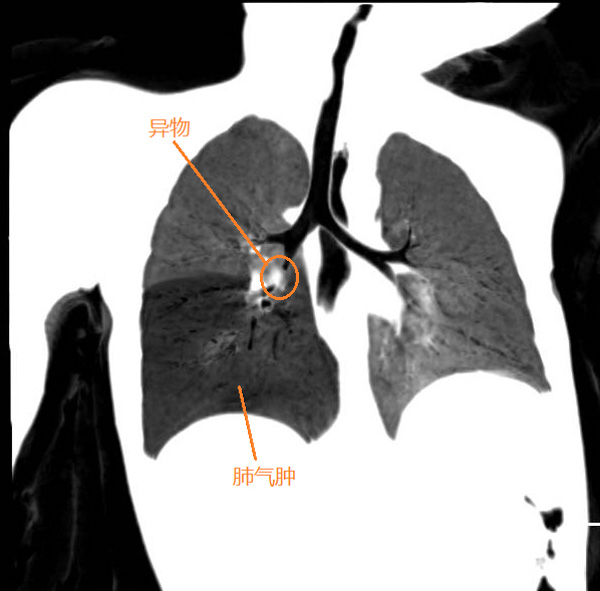

今年正月期间,正是举国上下防控新冠肺炎的最紧张阶段,很多医院对呼吸道的侵入性手术“谈虎色变”。就在那时,一张他带着防护眼镜跪在地上为一名1岁患儿手术的照片让不少人为之动容。磨宾宇说,患儿2天前在家吃橘子后,出现了烦躁、哭闹、拒食等表现,辗转了好几个医院,到我院时已经精神萎靡,呼吸稍显急促。检查发现患儿出现右肺气肿,高度怀疑支气管异物。

病情容不得犹豫,职责不允许退缩。身为主诊医生的他第一时间联系麻醉、手术室团队做好严格防护措施,患儿入院后的2小时,凌晨1点左右患儿被送进了手术室。因为麻醉和手术都必须经过患者气管,所以气管异物手术不能像常规手术一样插管麻醉后再从容的操作。加上儿童的气道狭窄,视野狭小,手术风险大,手术成败与窒息死亡往往就在2-3分钟之间,业内形容为“走钢丝的手术”。

情况紧急,他当机立断,直接双膝跪在地上为患儿进行了手术,不到2分钟时间,患儿气管内的异物被成功取出,小朋友的气紧立即缓解。他发现异物并不是橘子,而是一粒直径仅有3mm已经灰暗变软的花生仁,通过询问家长才知道,7天前小朋友吃过花生。